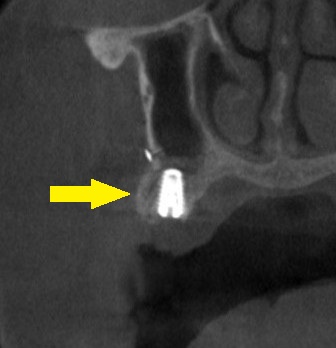

そこで、第二小臼歯部には、側方に人工骨を補填して、骨幅を増やす骨造成を行い、通常サイズのインプラントを埋入。

この方法で、患者様の了承が得られましたので、本日、インプラント埋入手術を施行しました。

下の写真下段が、手術後のCTです。